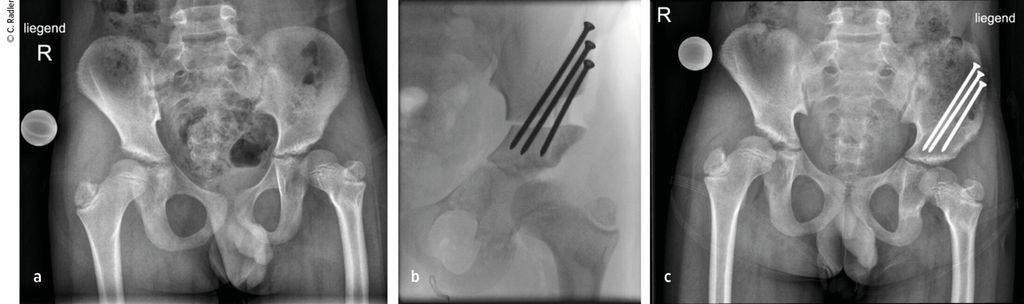

Der kongenitale Femurdefekt ist eine der spannendsten und komplexesten angeborenen Fehlbildungen in der Kinderorthopädie und in der klinischen Präsentation sehr vielgestaltig. Während auf den ersten Blick die Verkürzung des Beins/des Femurs augenscheinlich ist, sind es die assoziierten Veränderungen an Hüfte und Kniegelenk, welche die Therapie herausfordernd machen und vor einer Verlängerung adressiert werden müssen.

Zu den angeborenen Längsdefekten der unteren Extremität zählen neben dem kongenitalen Femurdefekt (CFD) die Fibulahemimelie (FH) und die Tibiaaplasie/-hemimelie. Der Femurdefekt reicht von einer milden Verkürzung des Femurs bis zu seinem fast vollständigen Fehlen, und auch die Fibulahemimelie kann sich von einer milden Verkürzung des Unterschenkels bis zu einer massiven Verkürzung mit schweren Veränderungen am Sprunggelenk präsentieren. Der CFD und die FH kommen fast immer gemeinsam vor, wobei die meisten Fälle eine klare Dominanz der einen oder anderen Pathologie zeigen und die sekundäre Deformität sich oft nur durch minimale Veränderungen an Knochen oder Gelenk präsentiert. Die Tibiaaplasie/-hemimelie ist oft mit Syndromen mit zusätzlichen Fehlbildungen oder Duplikaturen an Hand und Fuß verbunden. Diese Form ist mit einer Inzidenz von 1:1000000 sehr selten.